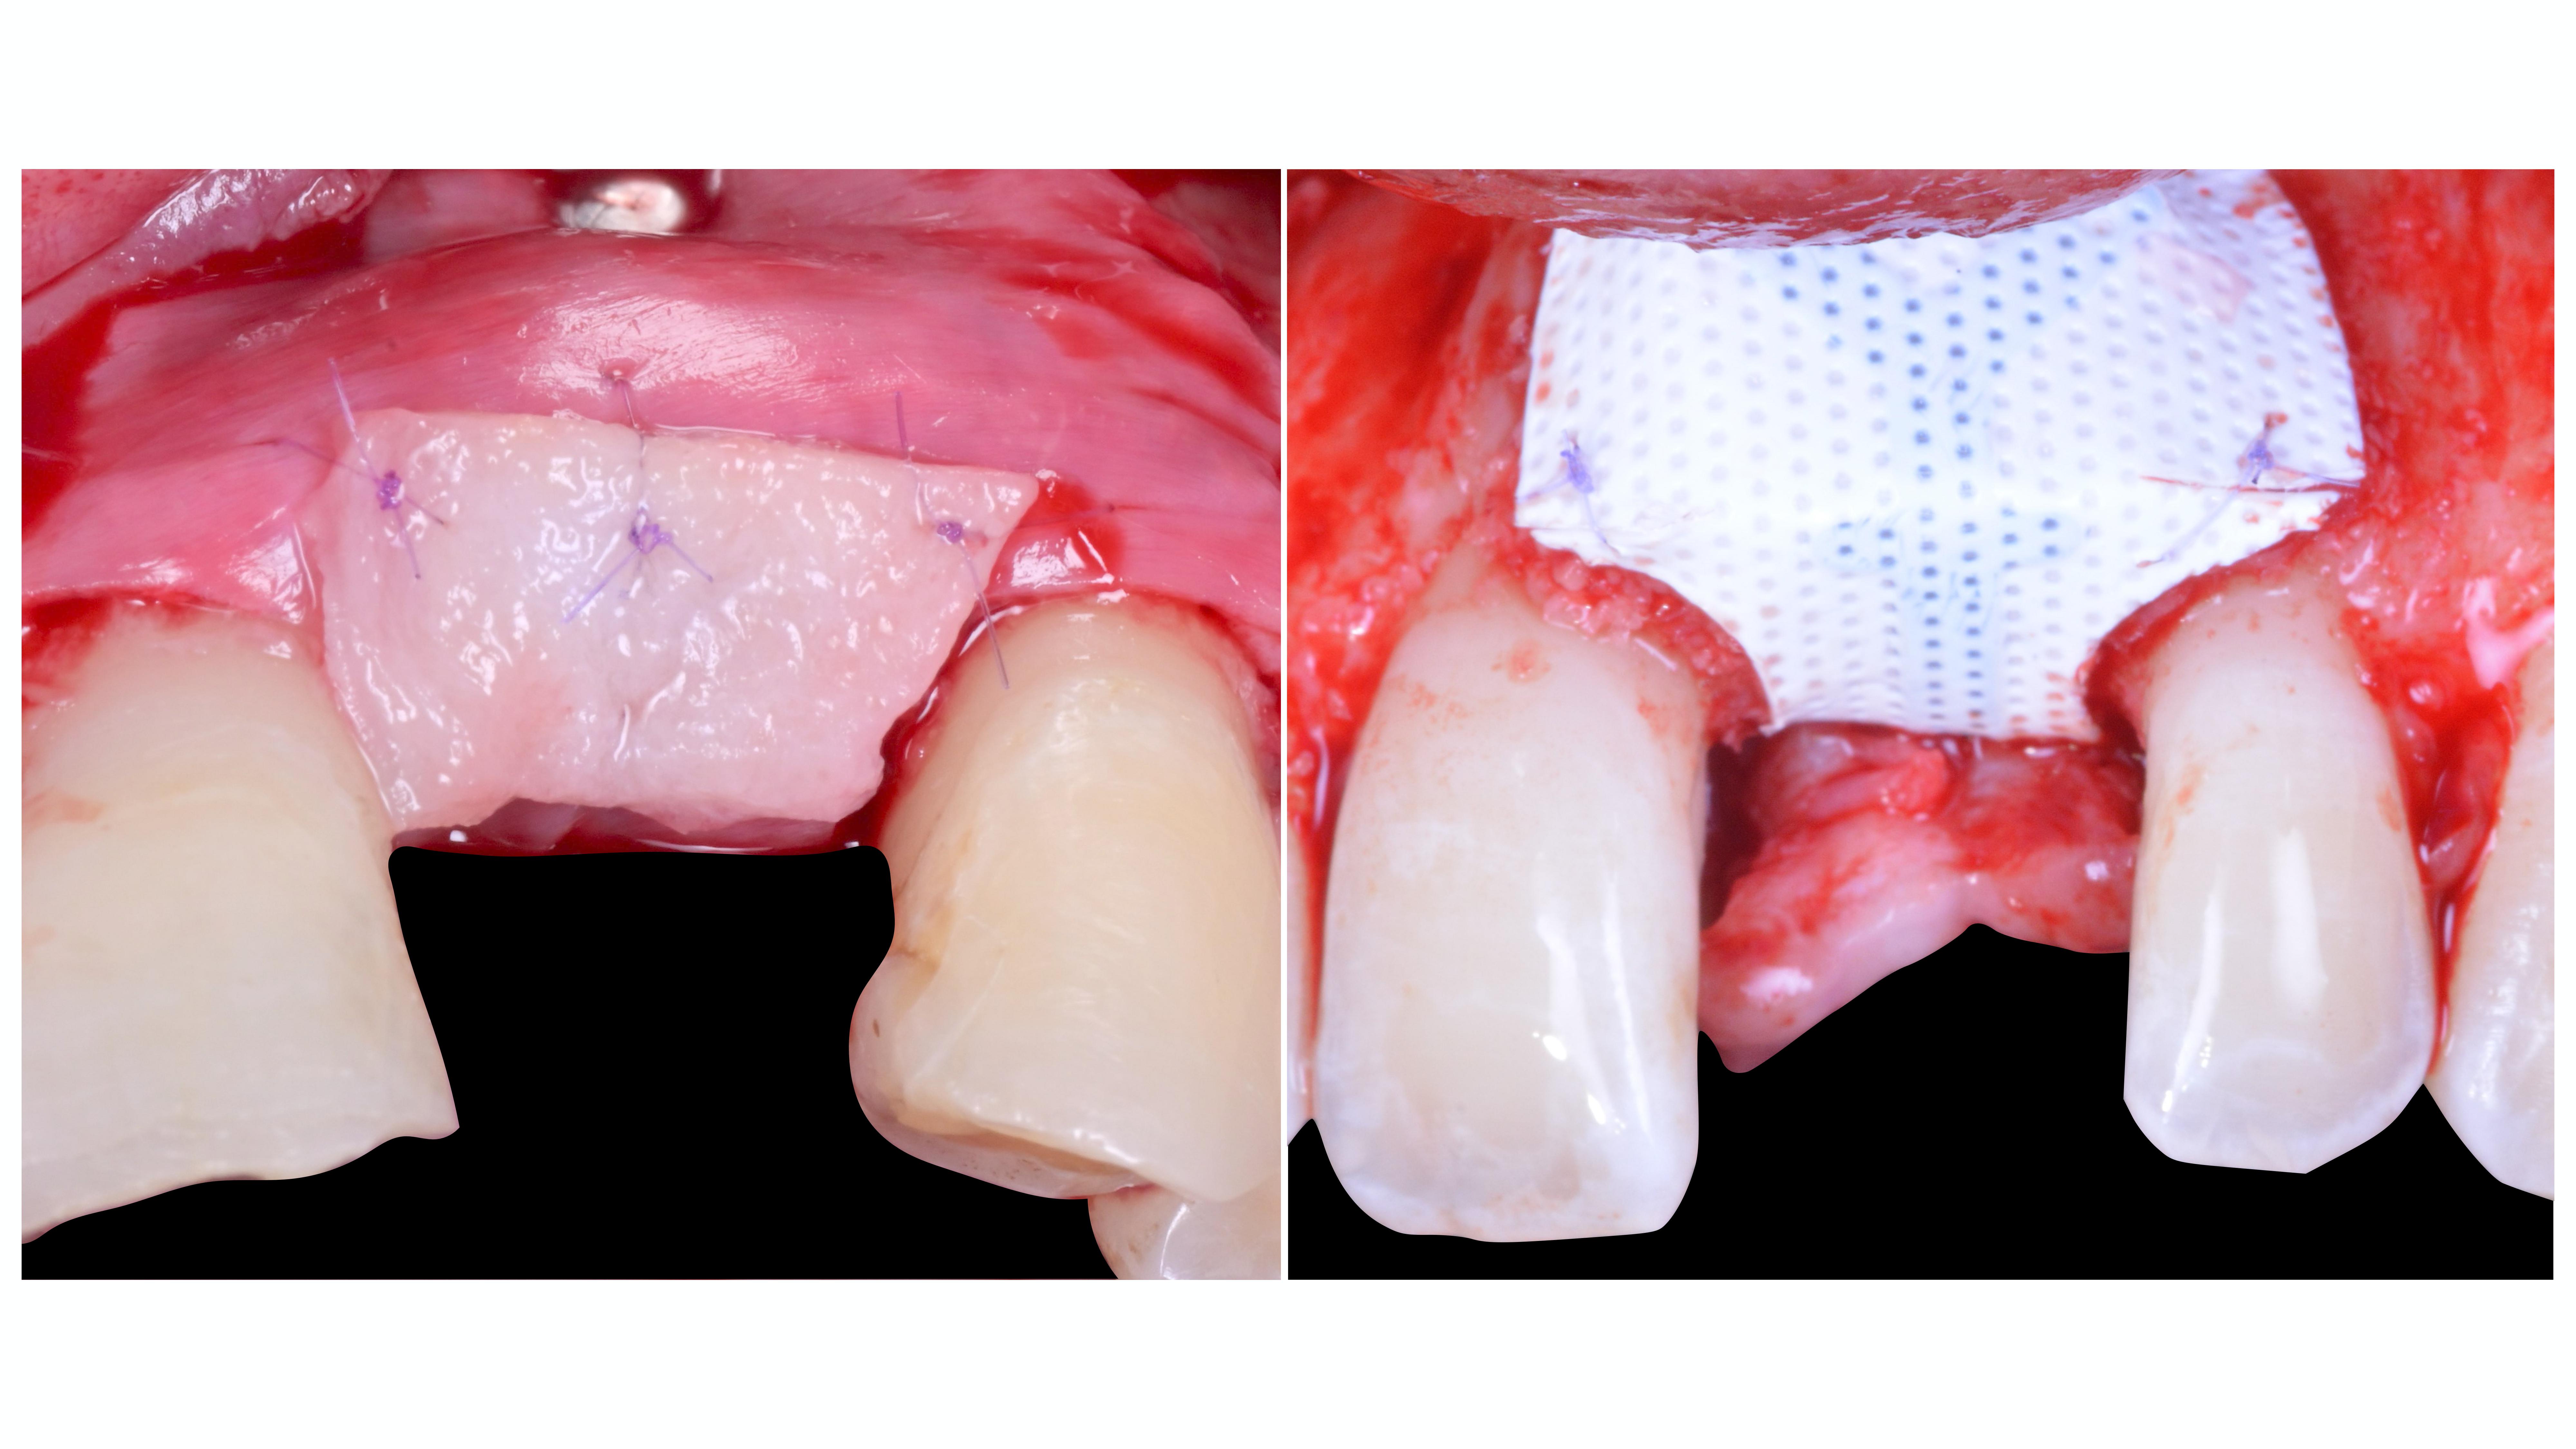

Drs Romain Chaleil et Aurélien Thollot

Les sutures sur membranes durant les régénérations osseuses guidées peuvent avoir divers objectifs :

- Stabiliser un tissu conjonctif à une membrane résorbable pour optimiser son positionnement et minimiser le nombre d’interventions.

- Suturer une membrane armée PTFE sur elle-même pour modeler la ROG et éliminer des zones irritatives au contact des muqueuses sous le lambeau vestibulaire.

Dans ces situations où les fils seront enfouis, la réaction inflammatoire minime lors de la résorption des fil 7/0 nous offre une qualité optimale de cicatrisation.

La solidité du fil Monosorb 7/0 et la finesse de l’aiguille permettent de réaliser ces gestes sereinement sans dilacérer les membranes.